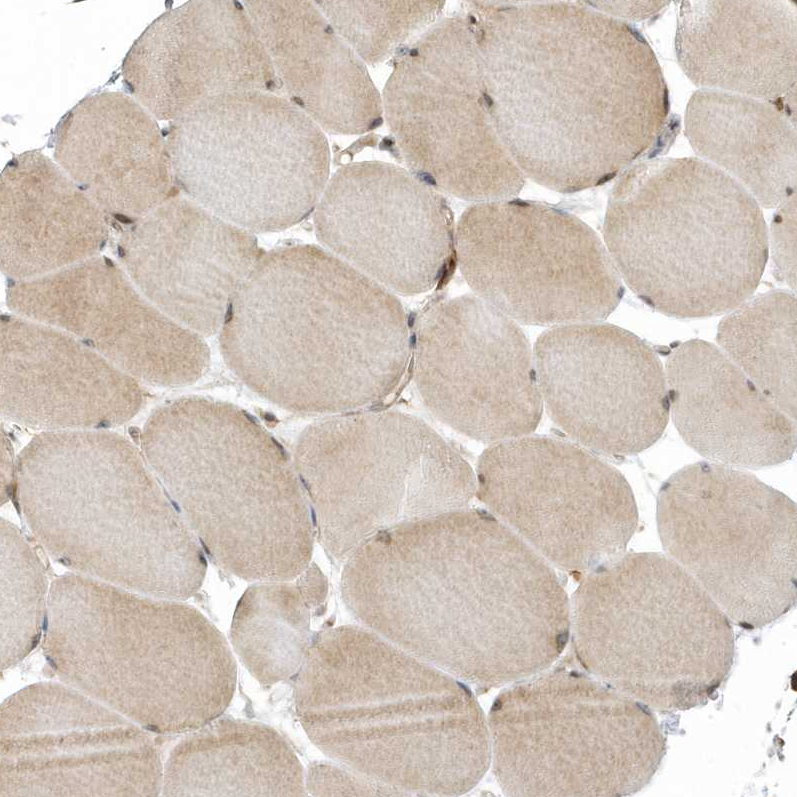

Immunohistochemical staining of human testis shows strong positivity in nuclear membrane in cells in seminiferous ducts with additional cytoplasmic positivity.